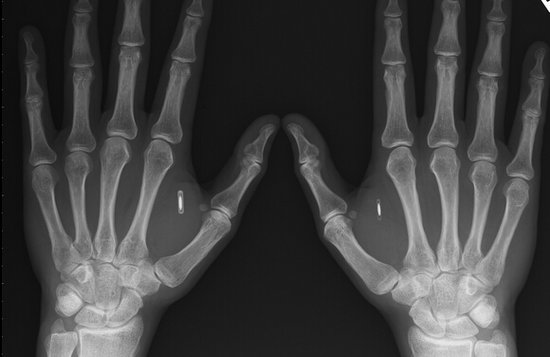

我们可能在电影中看到,植入人体的芯片可以追踪这个人的一举一动,而在现实生活,这一切已不是虚构。一位名叫罗伯特·纳尔逊(Robert Nelson)的人将一个NFC芯片植入到他的左手内,他本人经过测试发现,这种尝试有一定的“积极”意义。这哥们还打算让这颗NFC的芯片用在自己的家门和车库门上。

纳尔逊体内的芯片是由一家名为Dangerous Things公司提供,全名为兼容NFC技术的13.56MHz NTAG216 RFID,这款芯片有12毫米长,2毫米厚。芯片外壳是由具备生物相容性物质构成。纳尔逊本人花费了100美元通过一次无菌注射将这种芯片植入体内。需要说明的是,Dangerous Things产品并未获得FDA及其他监管机构的临床测试认证,因此这次尝试只是一次个人行为。